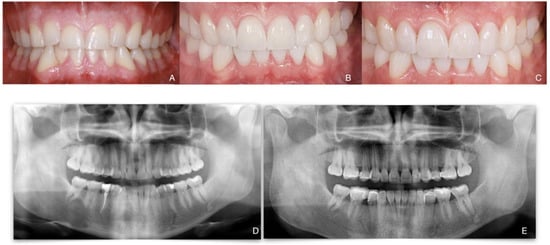

Total Rehabilitation Using Adhesive Dental Restorations in Patients with Severe Tooth Wear: A 5-Year Retrospective Case Series Study

3. Results